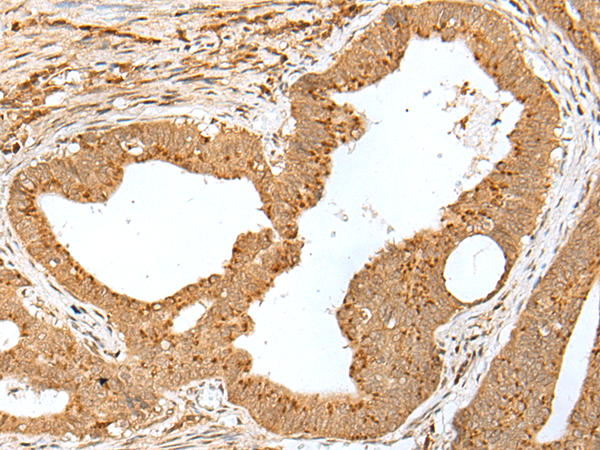

IHC positive control: |

Human gastric cancer and human tonsil |